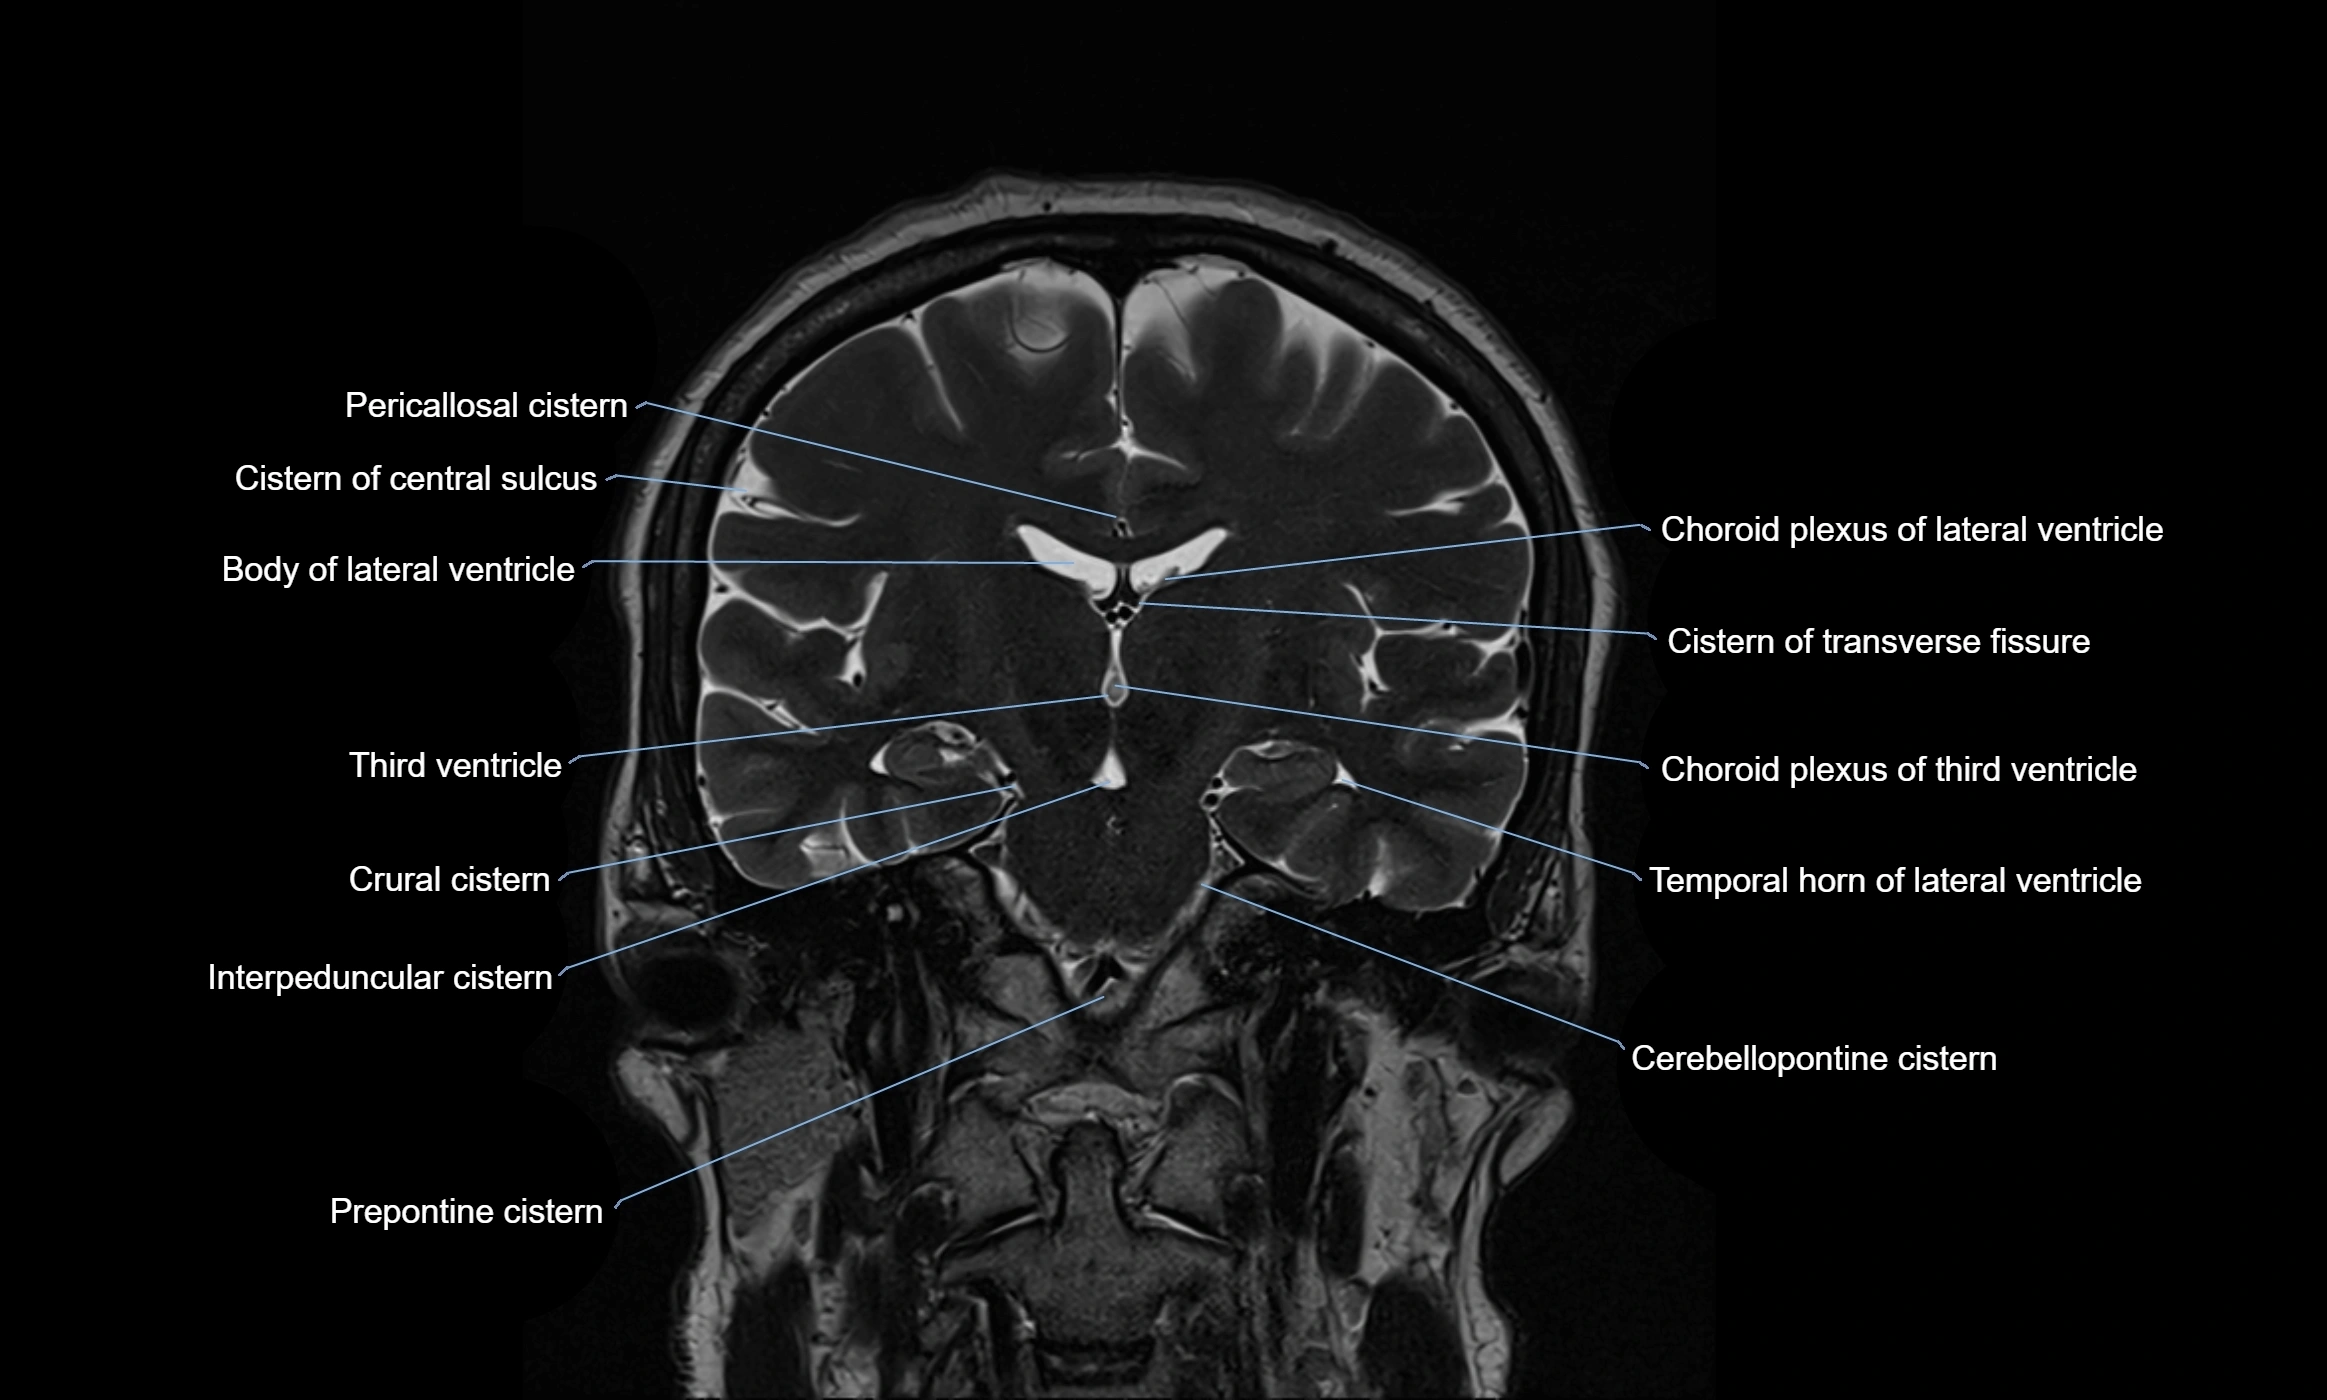

Ambient cistern

The ambient cistern is a paired, narrow, and elongated subarachnoid space located bilaterally along the lateral aspect of the midbrain. It serves as a conduit between the interpeduncular cistern anteriorly and the quadrigeminal cistern posteriorly. This cistern houses critical neurovascular structures, including parts of the posterior cerebral artery, superior cerebellar artery, trochlear nerve (cranial nerve IV), and the basal vein of Rosenthal. It plays an important role in the circulation of cerebrospinal fluid (CSF) and provides an anatomical corridor for various vessels and nerves passing around the midbrain.

MRI Appearance

• T2-weighted images:

• The cistern is hyperintense (bright) due to the high water content of CSF.

• Encapsulated vessels and nerves are seen as flow voids or hypointense lines within the bright background.

MRI images

image